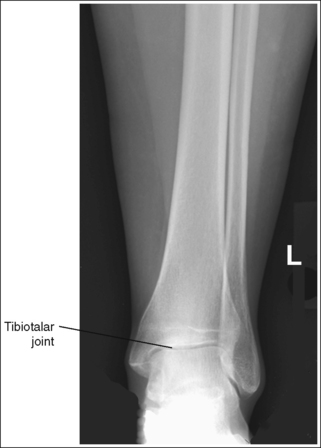

The tibiotalar joint space is open, and the tibia is demonstrated without foreshortening.

• The tibiotalar joint is open and the tibia is demonstrated without foreshortening if the patient's lower leg was positioned parallel with the IR and the central ray was centered at the level of the tibiotalar joint.

• Evaluating the openness of the tibiotalar joint. On an AP ankle projection, determine whether an open joint was obtained and whether the tibia is demonstrated without foreshortening by evaluating the anterior and posterior margins of the distal tibia. On an AP ankle projection with accurate positioning, the anterior margin is demonstrated approximately 0.125 inch (3 mm) proximally to the posterior margin (see Figure 6-48). If the proximal lower leg was elevated or the central ray was centered proximal to the tibiotalar joint, the anterior tibial margin is projected distally, resulting in a narrowed or obscured tibiotalar joint space (see Image 34). If the distal lower leg was elevated or the central ray was centered distal to the tibiotalar joint, the anterior tibial margin is projected more proximally to the posterior margin than on an AP ankle projection, expanding the tibiotalar joint space and demonstrating the tibial articulating surface (see Image 35).

• The tibiotalar joint space is open and the tibia is demonstrated without foreshortening when the patient's lower leg was positioned parallel with the IR and the central ray was centered at the level of the tibiotalar joint (see Figure 6-52).

• Evaluating the openness of the tibiotalar joint. On an AP oblique ankle projection, you can determine whether the positioning and central ray alignment goals have been met by evaluating the anterior and posterior margins of the distal tibia. On an AP oblique ankle projection with accurate positioning, the anterior margin should be visualized approximately 0.125 inch (3 mm) proximal to the posterior margin. If the proximal lower leg was elevated or the central ray was centered proximal to the tibiotalar joint, the anterior tibial margin is projected distally, resulting in a narrowed or obscured tibiotalar joint. If the patient's distal lower leg was elevated or the central ray was centered distal to the tibiotalar joint, the anterior tibial margin is projected too far proximal to the posterior margin, expanding the tibiotalar joint space and demonstrating the tibial articulating surface (see Images 39 and 40).